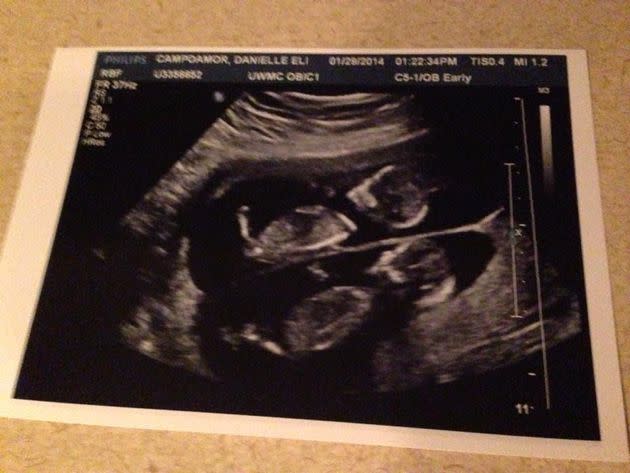

A little over nine months earlier, at a Planned Parenthood tucked away in a nondescript building in South Seattle, an overly kind ultrasound technician calmly informed me that I wasn’t just pregnant — I was pregnant with twins. After accidentally blurting out a string of expletives and requesting the technician count the embryos again … and again … and again … I left the exam room armed with half-a-dozen fuzzy black-and-white pictures of two alien-looking sacs and a full-blown smile.